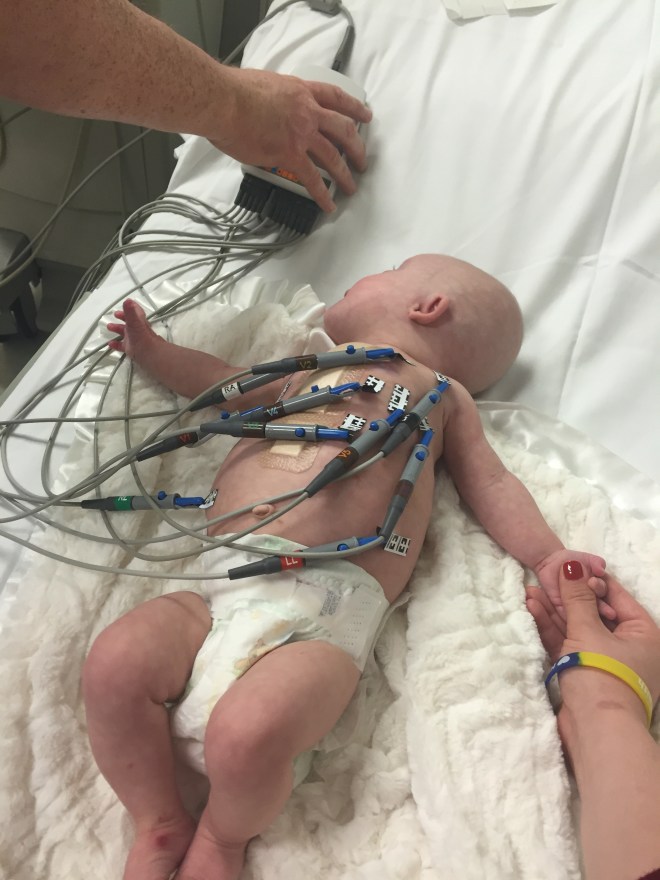

Kenlee getting her EKG.